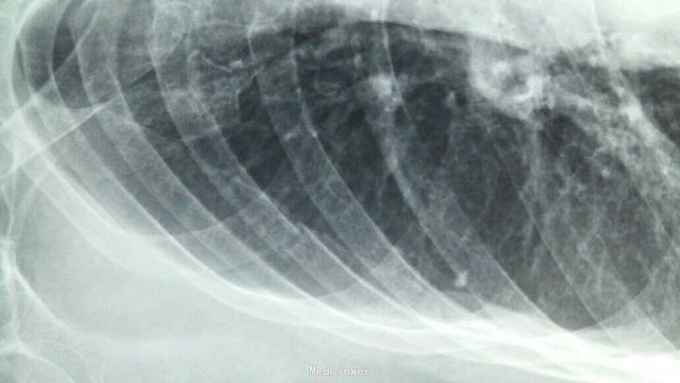

摔伤后胸痛、胸闷1天 1天前在自家劳动时摔伤胸部,伤后胸痛、胸闷,呼吸急促,活动后加重,不敢平卧,为诊治来院。

右侧胸部第4肋及第5胸肋关节处可触及骨摖感,触痛阳性。右肺呼吸音减弱。

1、右侧第4肋骨骨折;2、右侧第5胸肋关节脱位。 1、局部胸带外固定;2、促进骨愈合药物;3、平喘、化痰、预防感染;4、密切观察病情变化,随时复查。